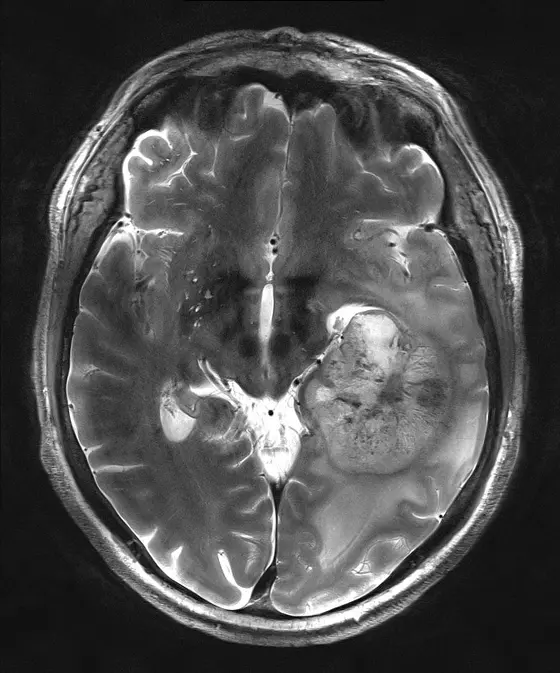

Magnetresonanztomographische Aufnahmen eines Glioblastoms